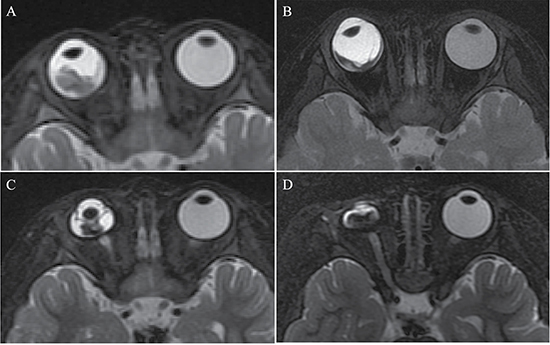

Figure 1: Clinically diagnosed retinoblastoma in a 24-month old male (patient 1). (A–H) An orbital mass is shown at the right globe with the tumor totally or partially covering the optic disk before intra-arterial chemotherapy (IAC), which demonstrates a slightly higher signal intensity than the ocular fluid as observed in axial T1-weighted magnetic resonance imaging (MRI) (A), low signal intensity (arrow) in the axial T2-weighted MRI (B) and moderate enhancement of the retinoblastoma (arrow) in the axial contrast-enhanced, T1-weighted, fat-saturated MRI (C). The axial DWI (D) shows restricted diffusion (arrow) in the tumor, a finding indicative of high tumor cellularity. (E–H) The axial T2-weighted MRI (F) shows that the size of the tumor is diminished after treatment with IAC and demonstrates a low signal intensity of the residual tumor foci partially covering the optic disk (arrow). The axial contrast-enhanced T1-weighted, fat-saturated MRI (G) shows non-enhancement of the residual tumor foci with comparison to the high signal intensity found in the T1-weighted MRI (E). The axial DWI (H) shows the low signal intensity of the residual tumor foci (arrow).

Figure 2: Clinically diagnosed retinoblastoma in a 44-month-old female (patient 2). (A–H) The orbital origin of the tumor was located in the equator of the left globe with the tumor location far from the optic disk, demonstrating a slightly higher signal intensity than the ocular fluid (arrow) in axial T1-weighted MRI (A), low signal intensity (arrow) in the axial T2-weighted MRI (B) and moderate enhancement of the retinoblastoma (arrow) in the axial contrast-enhanced T1-weighted, fat-saturated MRI (C). The axial DWI (D) shows restricted diffusion (arrow) in the tumor. (E–H) A small amount of the residual tumor foci is shown (arrow) in the axial T2-weighted MRI (F) after three cycles of IAC. The axial contrast-enhanced T1-weighted, fat-saturated MRI (G) shows non-enhancement of the residual tumor foci. The axial DWI (H) shows low signal intensity of the residual tumor foci (arrow).

The size of the tumors was obviously diminished after IAC in all 60 eyes, including the mean maximum diameter (t = 19.15; P < 0.001), the mean thickness (t = 18.49; P < 0.001), and the maximum cross-sectional area (t = 21.35; P < 0.001) (Figure 1 and Figure 2). Both group D and group E showed a significant difference in tumor size after IAC. There was no significant difference between the patients of group D and group E in the tumor size before or after treatment.

Enhancement of the tumor

Among the 60 eyes, compared to pretreatment, 51 tumors with moderate enhancement decreased to non-enhancement (Figure 1 and Figure 2) (n = 46; 90.2%) or slight enhancement (n = 5; 9.8%), and the other nine tumors changed from slight enhancement to non-enhancement (n = 9; 100%). Nodular enhancement of postlaminar optic nerves observed in six (10%) affected eyes before IAC disappeared after IAC (Figure 3).